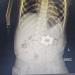

إنقاذ رضيع ابتلع 6 قطع مغناطيس في جراحة دقيقة بمستشفى الأطفال الجامعي بالمنصورة